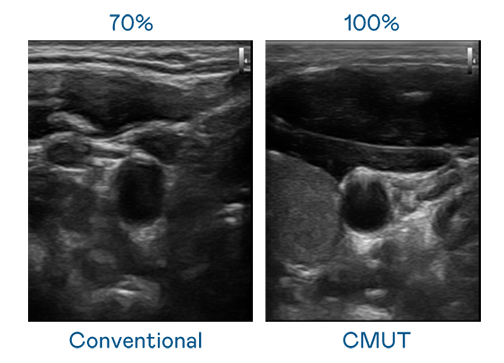

CMUT 技术是一种用电容式微机电元件来产生超音波讯号的技术。与传统 PZT 压电式技术相比,CMUT 频宽增加 30%,更宽频的超音波讯号让影像解析度大幅提升,是实现高影像品质医疗超音波扫描、促进精准医疗发展的关键技术。

大频宽带来超清晰影像

超音波影像的解析度高低,首先取决于探头能发出的讯号频宽。雷火竞技 CMUT 可提供高清晰的超音波讯号,提供高频宽、高灵敏度、影像纹理细节更高的超音波影像,协助医护人员缩短影像判读时间及利用精准的医疗影像进行诊断。